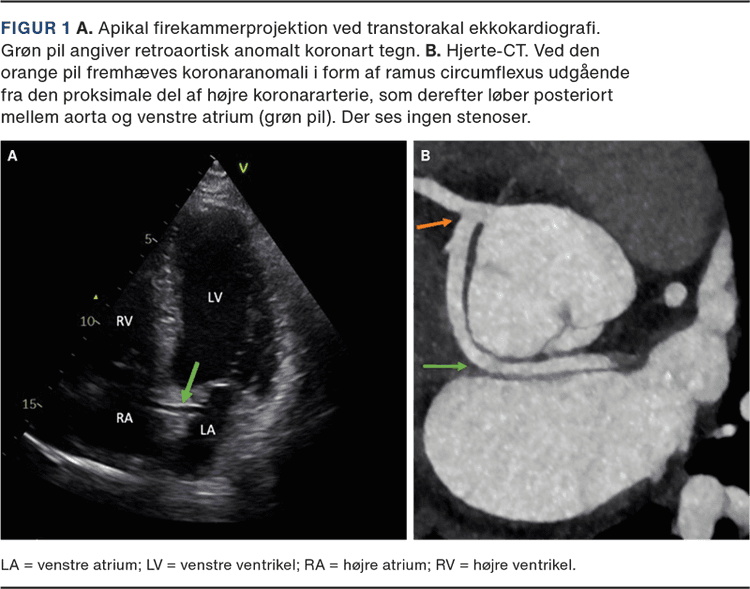

RAC-tegn ved ekkokardiografi | Ugeskriftet.dk